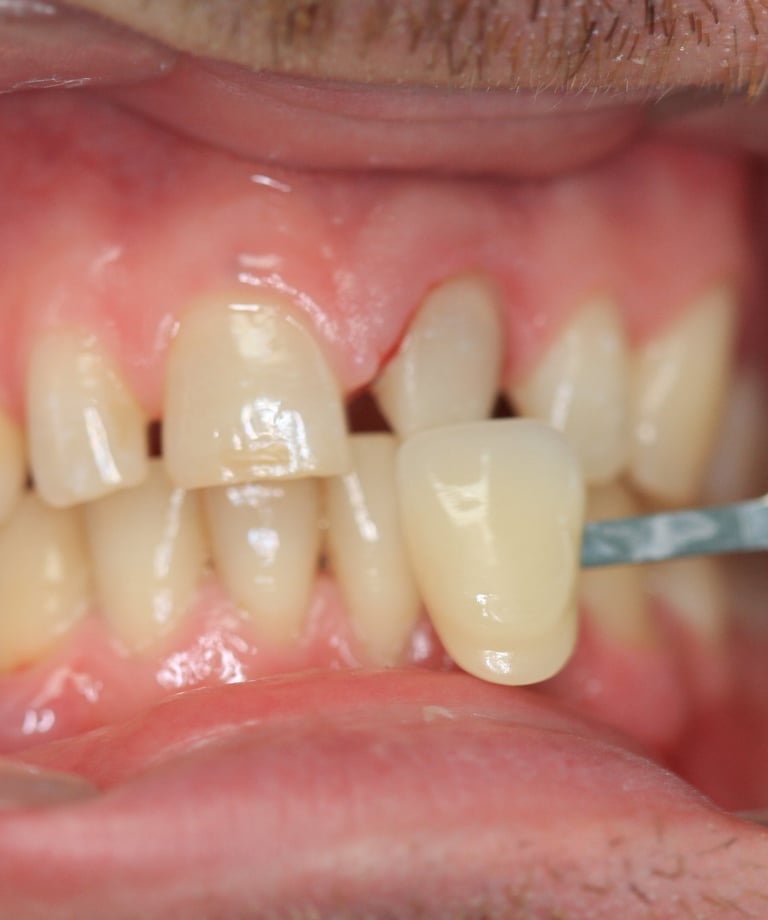

4. Prova estetica e inserimento della corona definitiva:

La nuova corona è stata prima provata per valutarne il colore, la forma e la precisione. Dopo aver ottenuto l'approvazione estetica, la corona è stata cementata utilizzando un cemento adesivo di ultima generazione, garantendo stabilità e una perfetta integrazione con i tessuti.